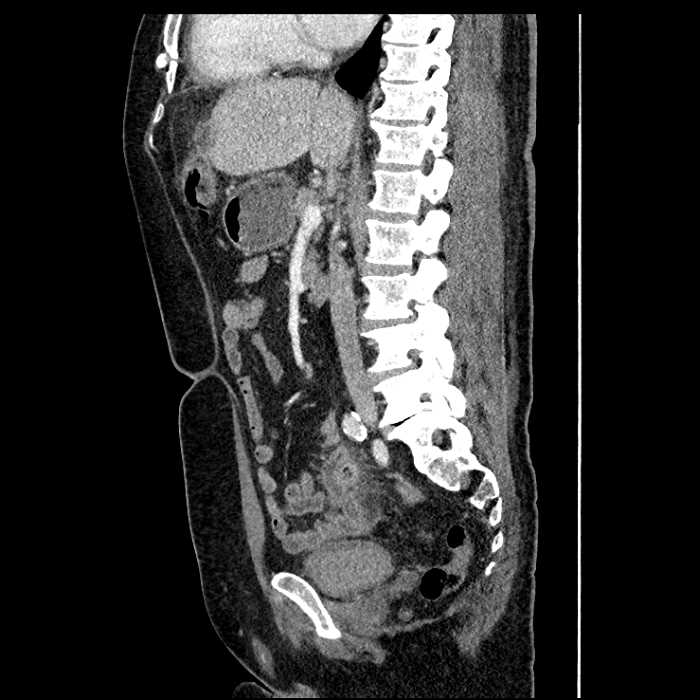

• Large fluid density structure in hepatic segments 7 and 8 measuring 10 x 7 x 7 cm with internal septation and circumferential ill-defined low density compatible with edema

• Peripherally enhancing subcapsular collections along the anterior margin of the left hepatic lobe measuring 3 x 1 cm and 2 x 1 cm

• Clearly marginated fluid density structure in segment 7 and several other scattered tiny hypodensities, which likely represent cysts

• Hepatic abscess

Acute sigmoid diverticulitis complicated by a small contained perforation and a large abscess in the right hepatic lobe. Additional small subcapsular abscesses along the anterior margin of the left hepatic lobe.

• The classic CT imaging appearance is a double target sign with internal low density surrounded by an internal enhancing rim (capsule) and a low density external rim (edema)

• Abscesses may be unilocular or multilocular

• Gas is present in a minority of cases

Hepatic abscess showing the double target sign with low density internally surrounded by a thin inner enhancing rim (red arrow) and ill-defined outer low density rim (yellow arrow). Blue arrow indicates an internal septation. Red arrows: additional smaller subcapsular abscesses. Red arrow: focal contained perforation associated with diverticulitis.